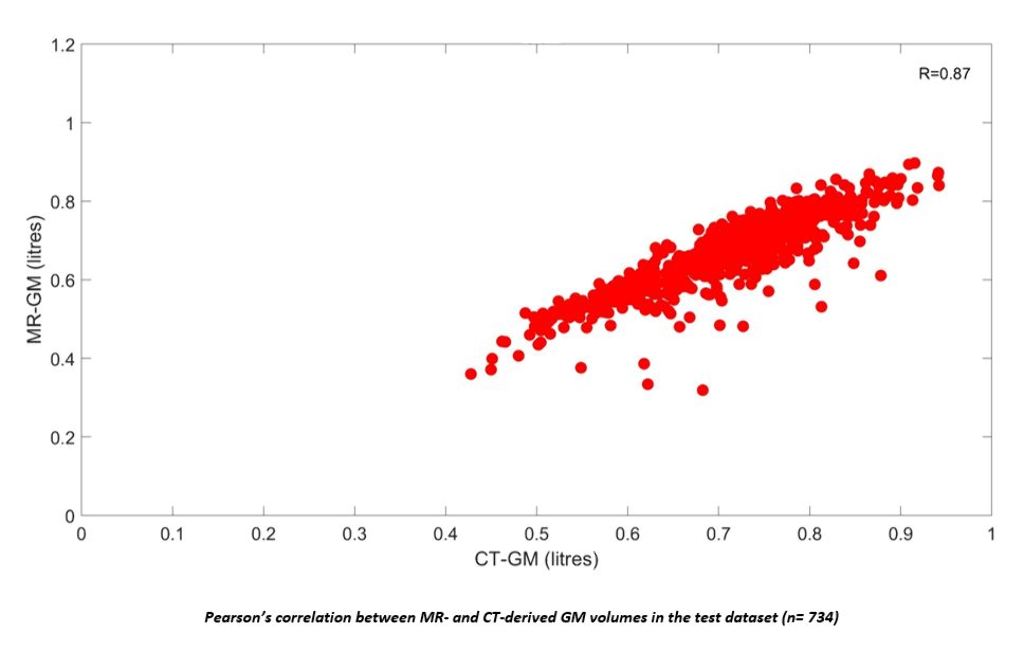

A first dataset was included from the Gothenburg H70 Cohort of which 734 participants (age= 70.42±2.6 years, 52.6% female) had paired CT and T1-weighted MRI scans. Grey matter (GM), white matter (WM), cerebrospinal fluid (CSF) and intracranial volume (ICV) segmentations were derived from MRI. A U-Net was trained on these to automatically predict the same tissue classes from CT, which were compared with MRI-segmentations for volumetric, spatial and shape similarity. Associations between CT-derived GM volumes (controlled for ICV), plasma NfL and mini mental state examination (MMSE) were tested using linear regressions. A second dataset including 300 participants with paired CT and MRI of which 30% had a clinical dementia diagnosis was included from the NUS MACC to validate diagnostic performance of the acquired measures.

In the H70 Cohort, high volumetric correlations and continuous Dice scores were observed between CT- and MRI-derived GM, WM, CSF and ICV. Lower CT-derived GM volumes were significantly correlated with higher plasma NfL (p=0.005) and lower MMSE scores (p= 0.001).